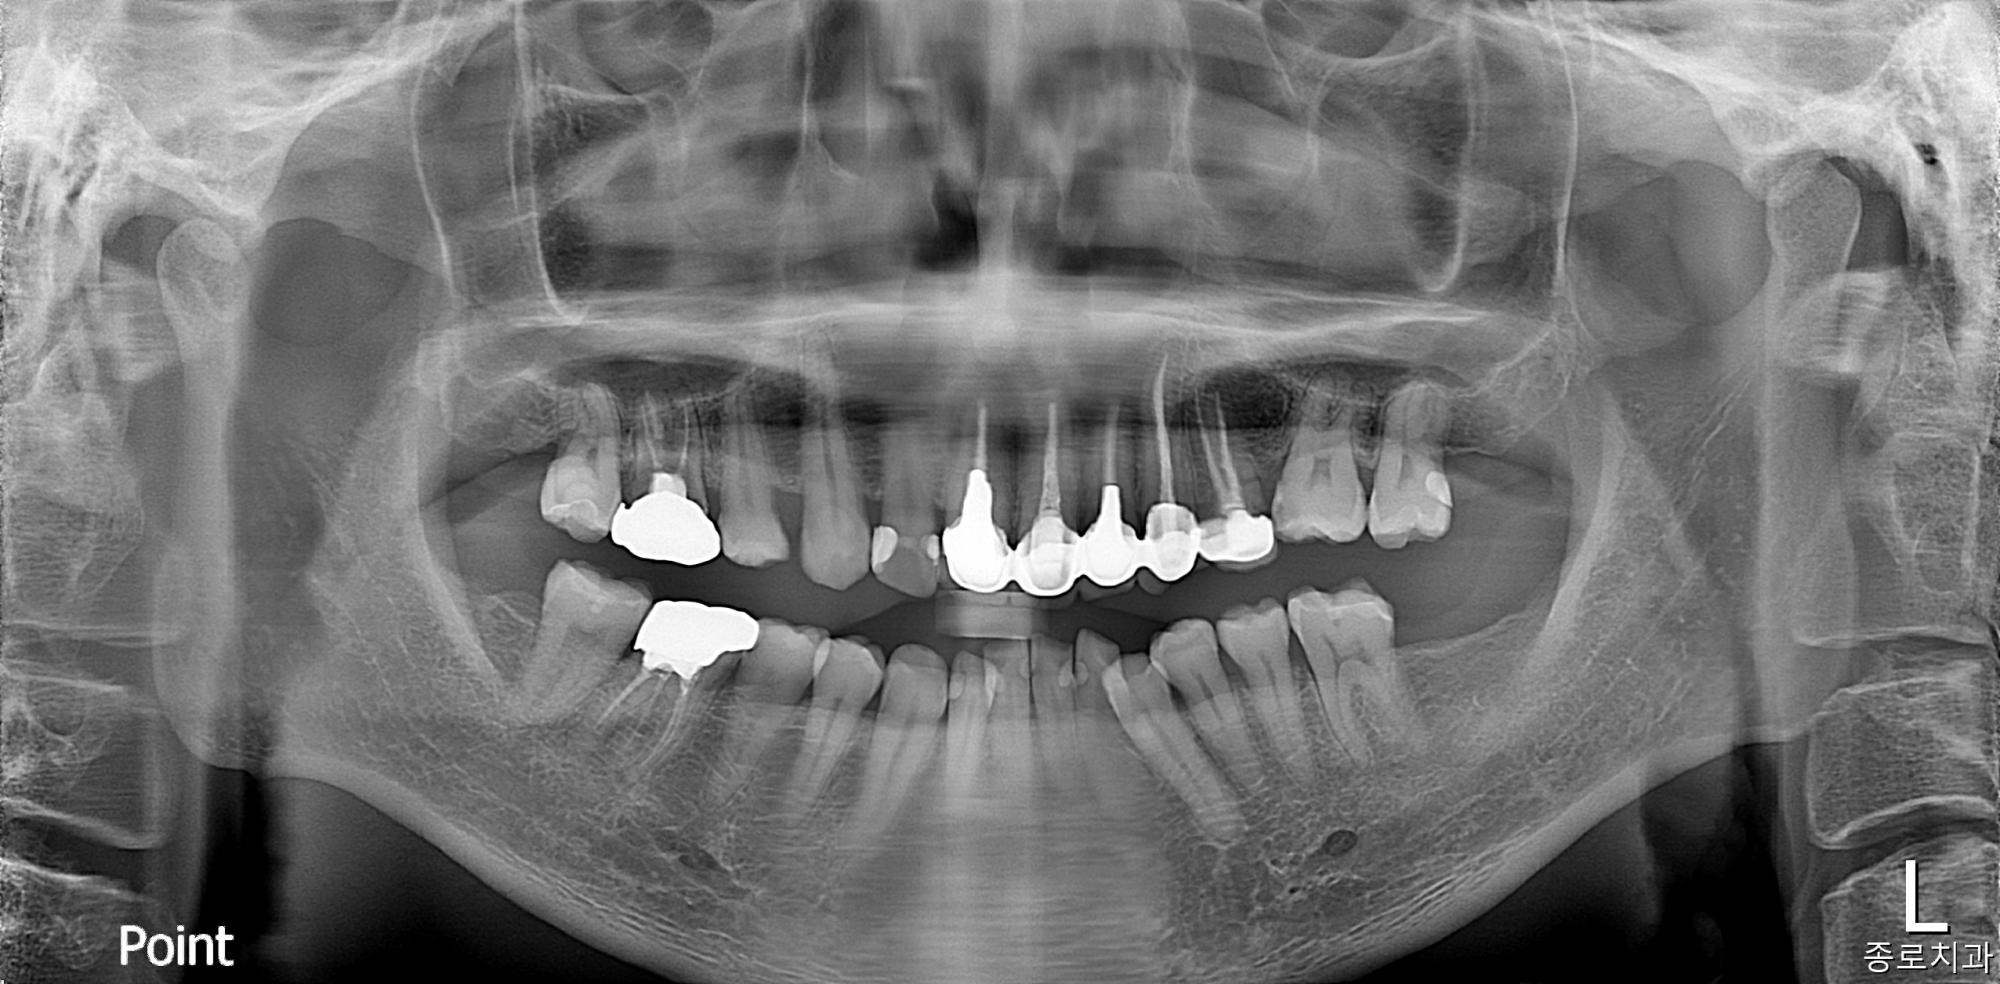

전/후사진

전/후 사진갤러리